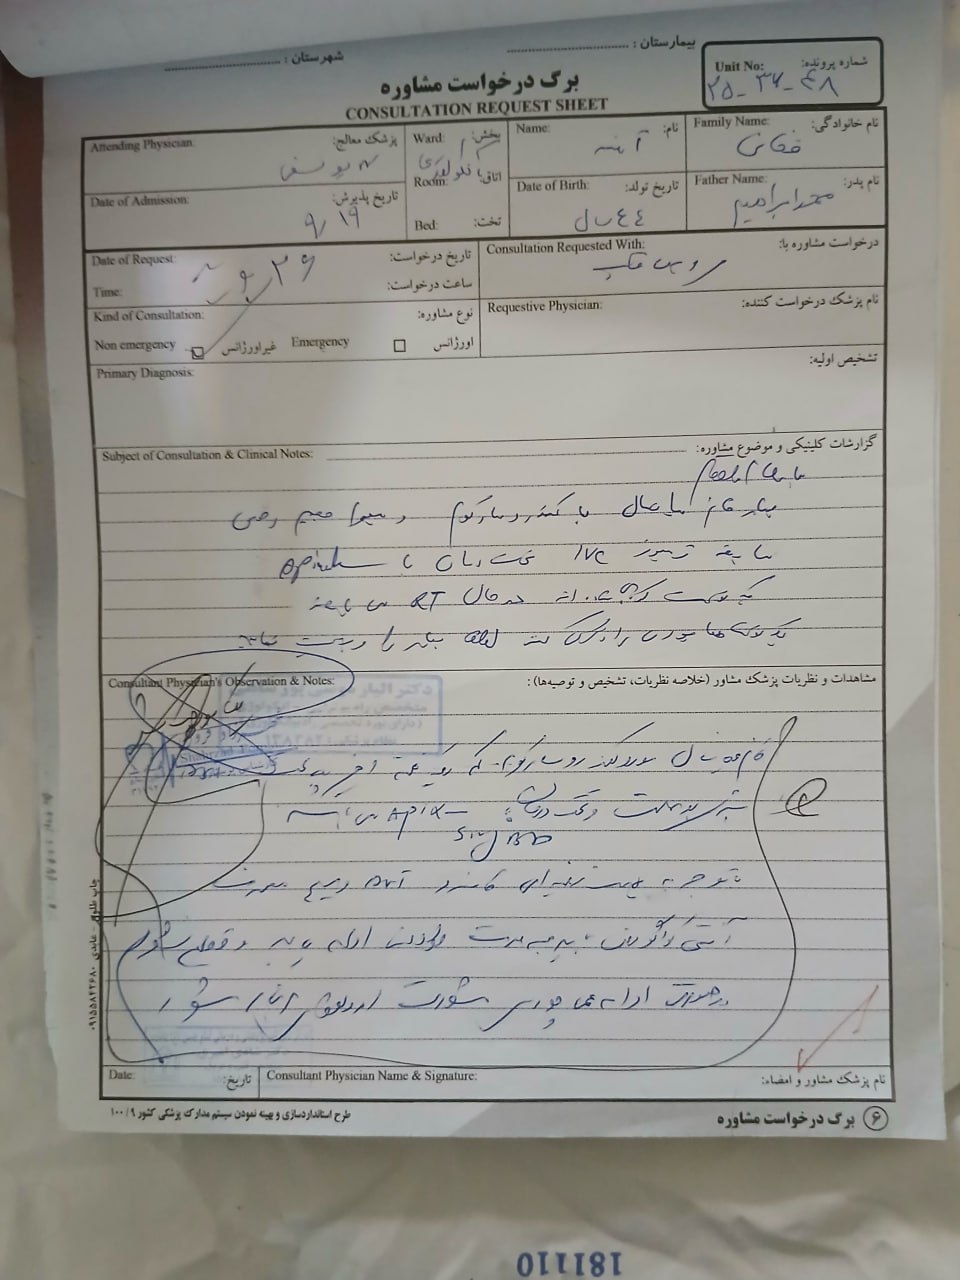

(تصویر مربوط به این مراجعه نیست) Other:

(تصویر مربوط به این مراجعه نیست) Other:

(تصویر مربوط به این مراجعه نیست) Other:

(تصویر مربوط به این مراجعه نیست) Other: